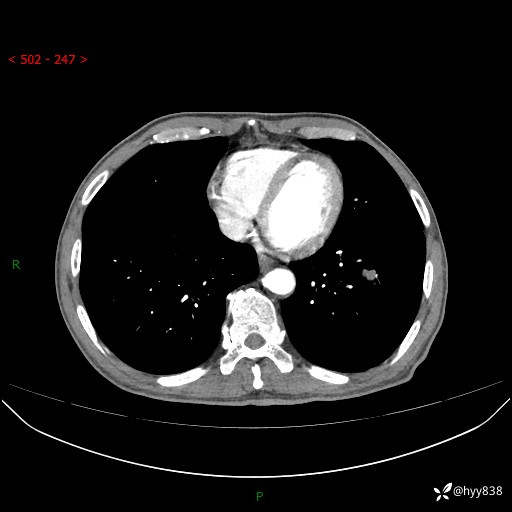

胸部CT平扫

增强动脉期+静脉期

各期CT值:38Hu 52hu 55hu